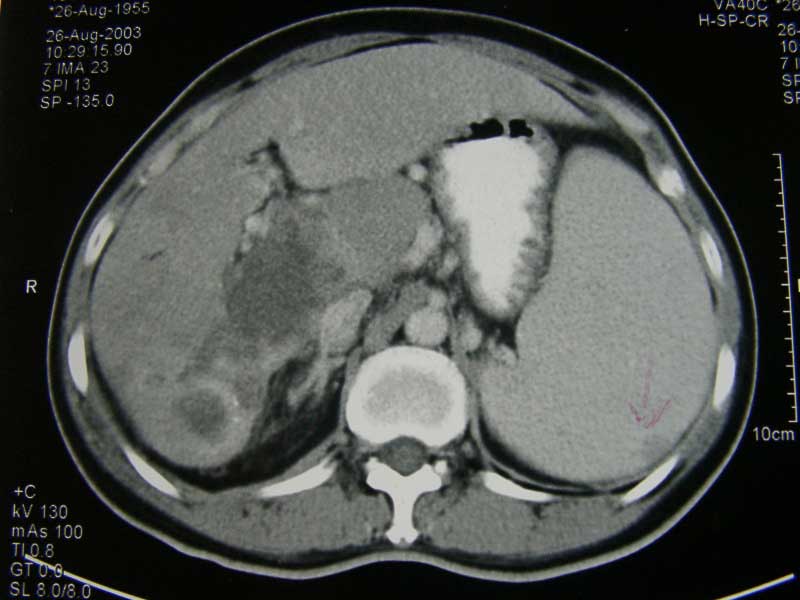

Pang (H5) adalah seorang pria berusia 61 tahun. Beberapa waktu pada bulan Februari 2008, ia mengalami rasa nyeri pada abdomen. Hasil ultrasonography menunjukan ada massa bulat berbatas tegal berukuran 5.2 x 5.3 x 6.5 cm pada lobus kanan heparnya (Segmen 6).

Pang dirujuk ke spesialis bedah di rumah sakit swasta. Hasil CT-scan menunjukan hepatoma lobus kanan dengan ukuran 8 x 7 x 8 cm pada segmen 6 dan 7. Pang menjalani operasi reseksi tumor pada 25 Maret 2008. Operasi ini menghabiskan biaya 20.000 RM.

Berat liver 305 gm, dengan ukuran 135 x 90 x 75 mm. Permukaan luar ireguler dan nodular. Nodul pada liver: hepatocellular carcinoma (karsinoma hepatoseluler) yang berdifernsiasi baik, tipe trabekuler, menginfiltrasi kapsula hepar, stadium III (T3NxMx).